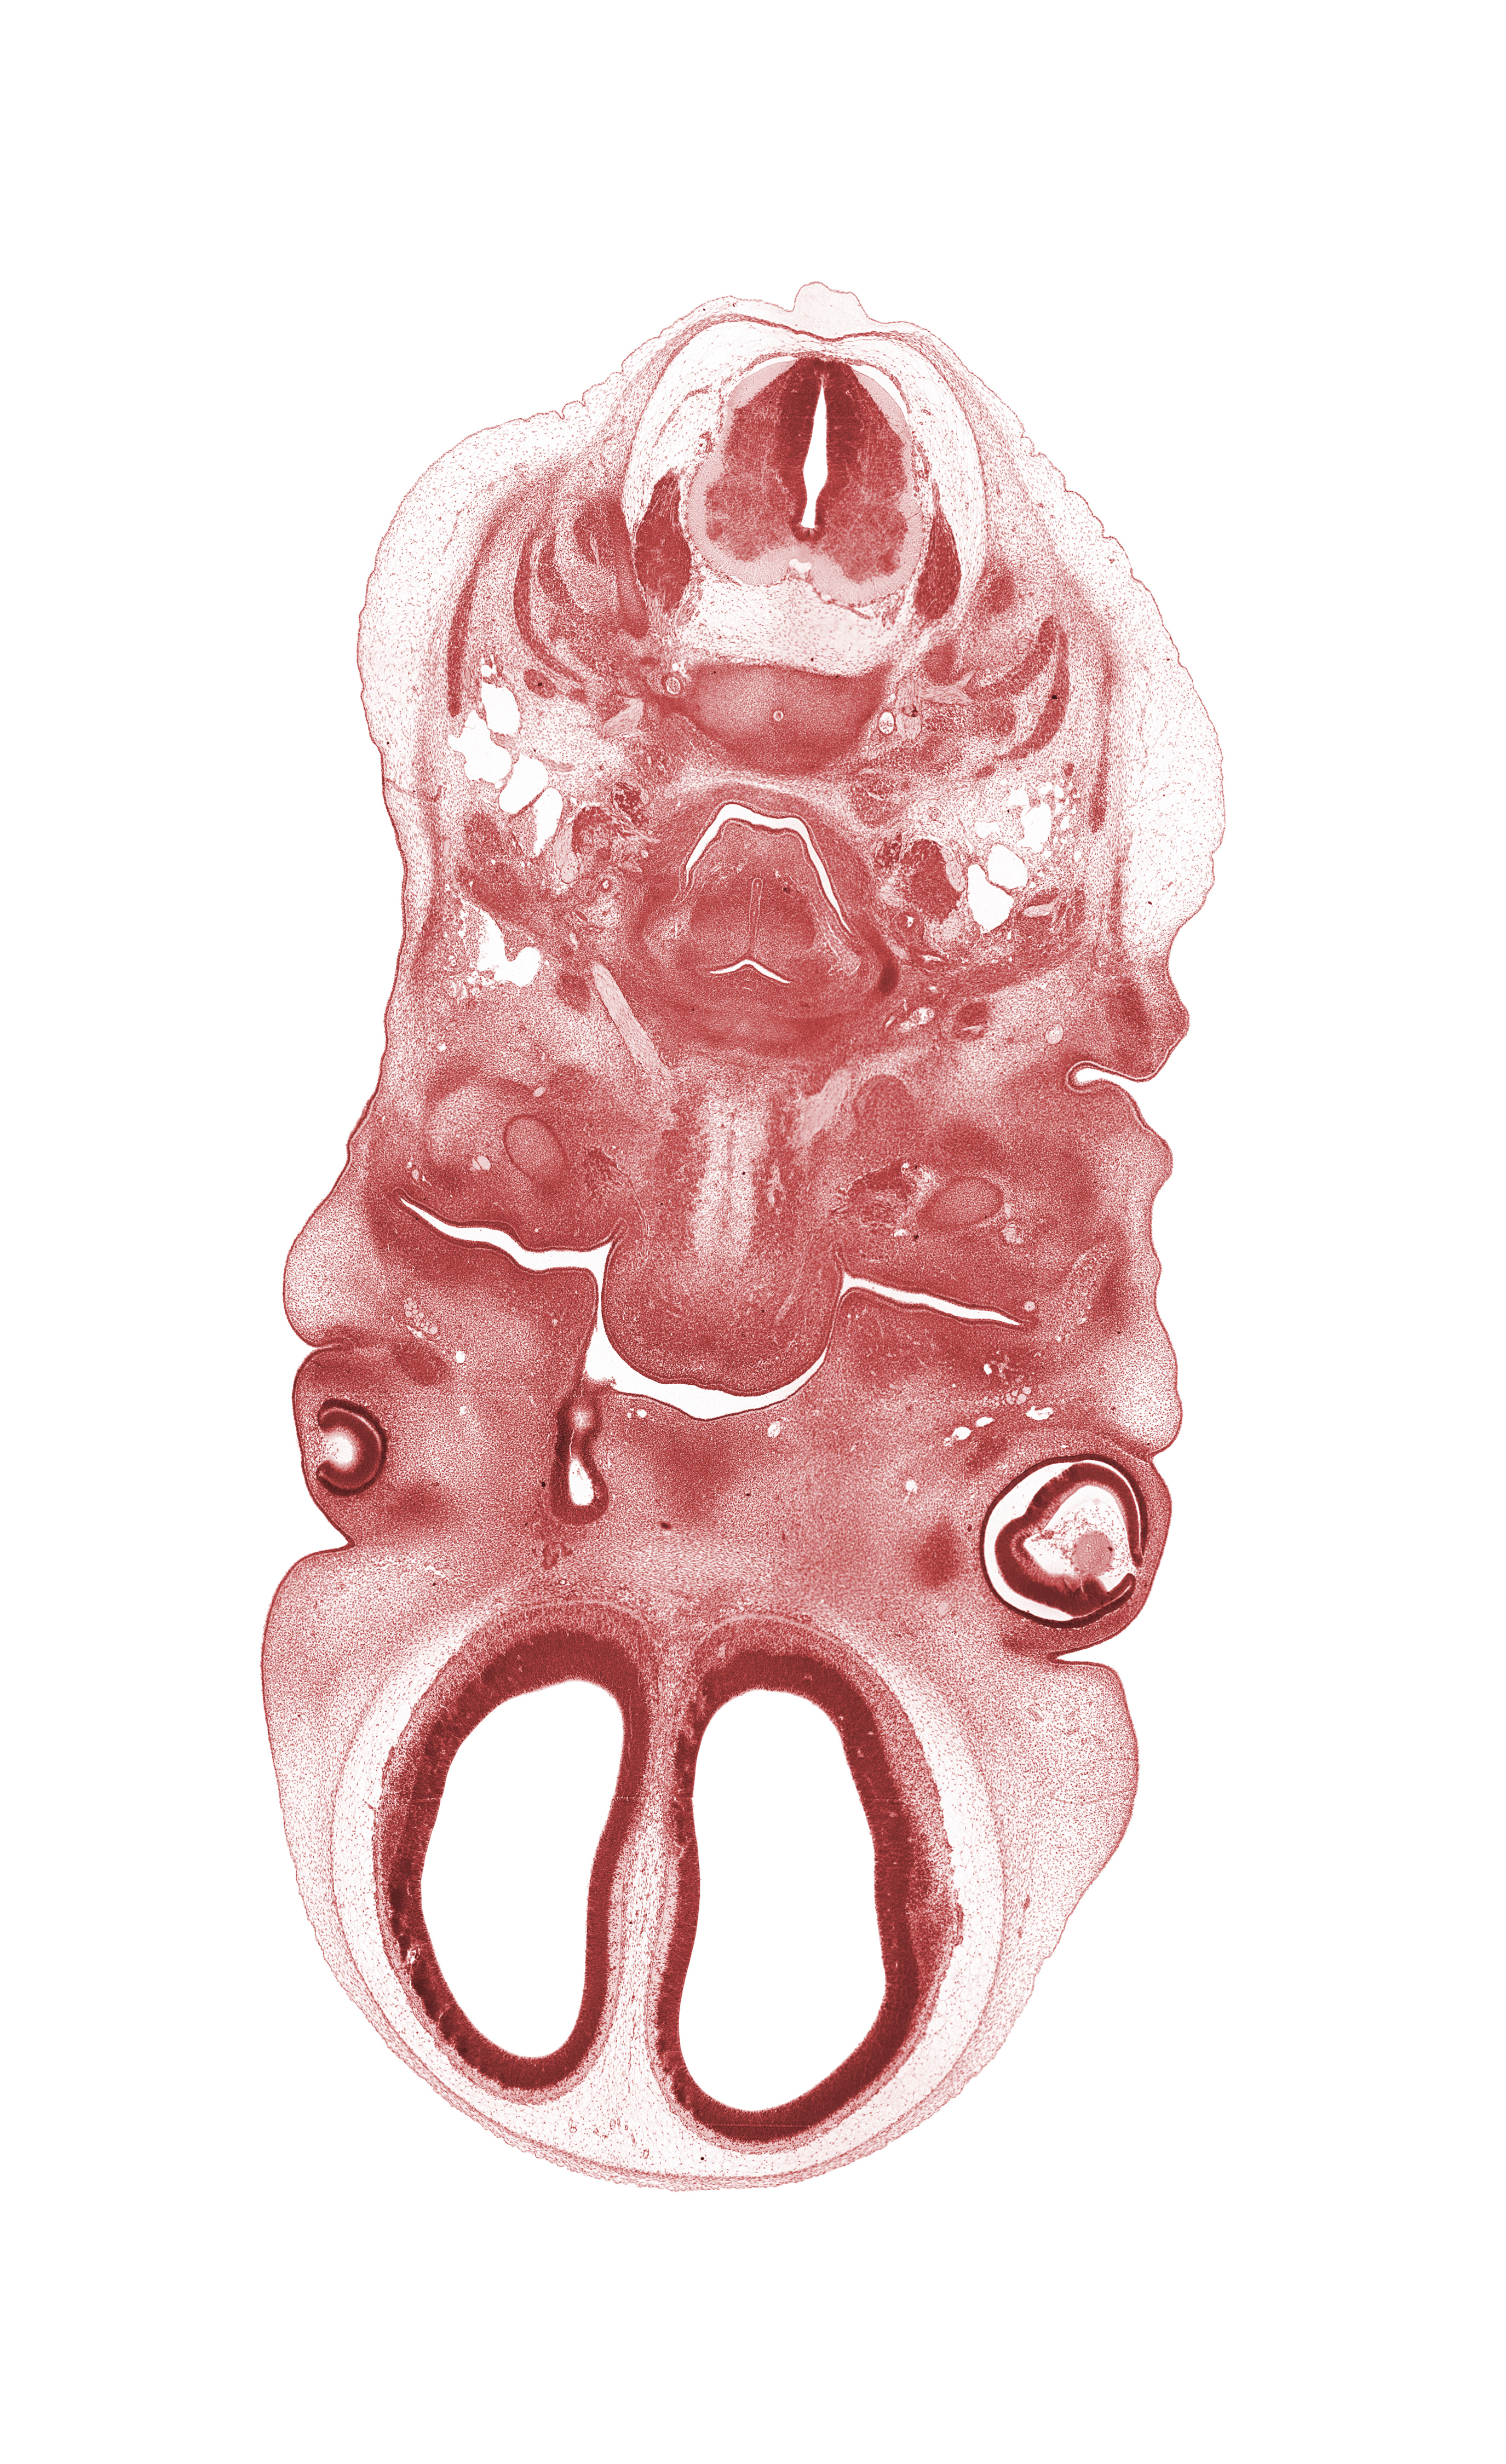

Carnegie Embryo #4430 | Location: 13-21

Keywords: C-2 / C-3 intervertebral disc, C-4 spinal ganglion, auricle, blastema of extrinsic ocular muscle, body of tongue, dorsal ramus of C-3 spinal nerve, edge of nasal cavity (nasal sac), falx cerebri region, internal carotid artery, laryngeal pharynx, maxillary venous plexus, oral cavity, palatine shelf, platysma muscle, precardinal vein, semispinalis capitis muscle, semispinalis cervicis muscle, splenius muscle, tongue septum, trapezius muscle, ventral ramus of C-3 spinal nerve

Source: The Virtual Human Embryo.